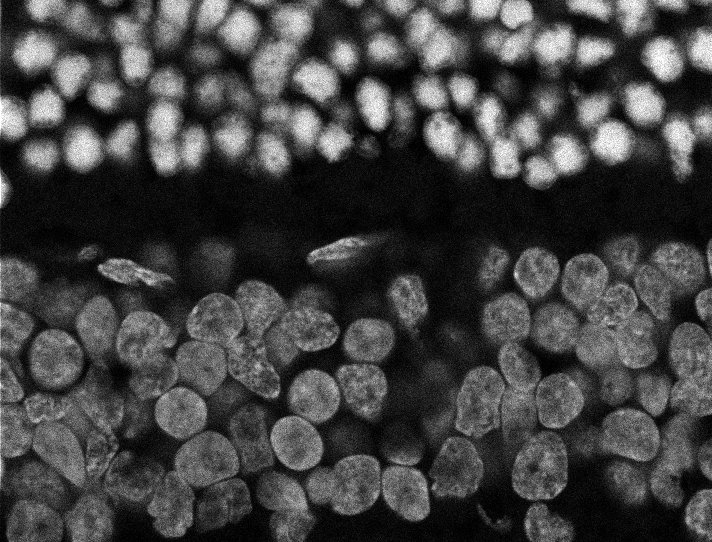

Nuclei

Nuclei - Bis

Nuclei - Bip